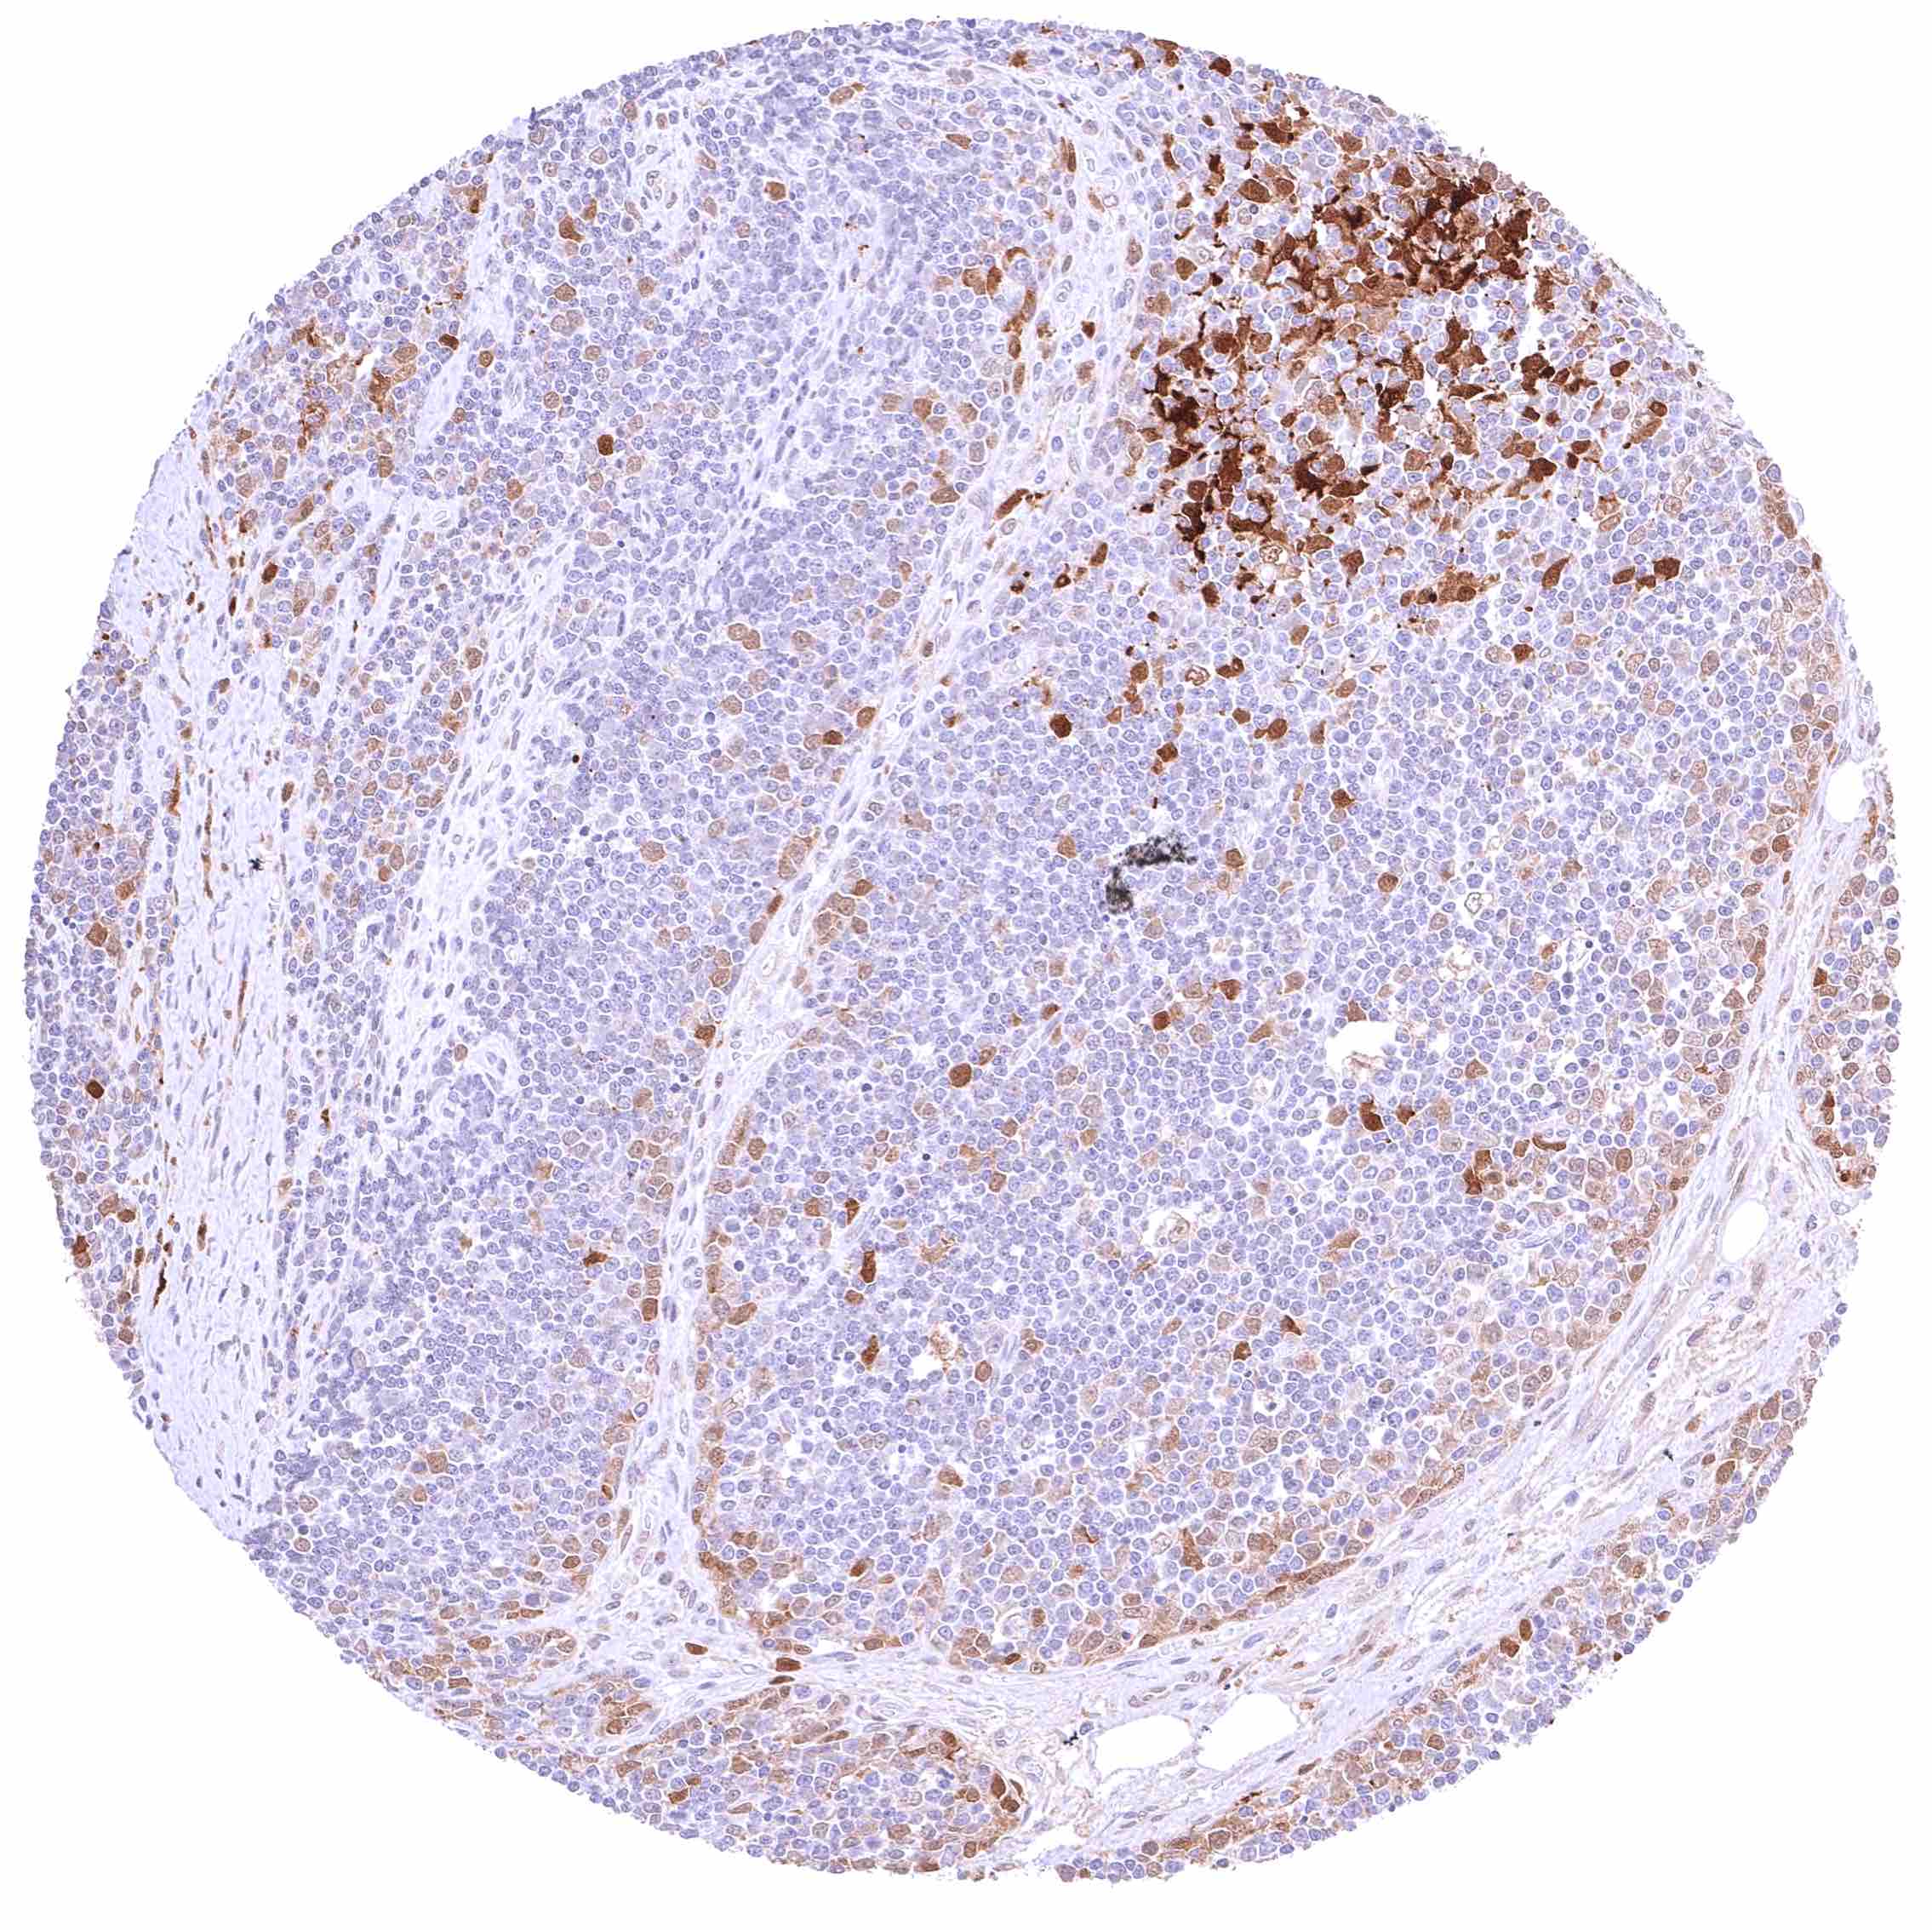

Lymph node – At least a weak cytoplasmic GSTP1 positivity occurs in all cells of this sample.

Lymph node – Nuclear and cytoplasmic GSTP1 positivity is limited to a small subset of cells in this sample.

Spleen – At least a weak cytoplasmic GSTP1 positivity occurs in all cells of this sample.

Spleen – Nuclear and cytoplasmic GSTP1 positivity is limited to a small subset of cells in this sample. .jpeg